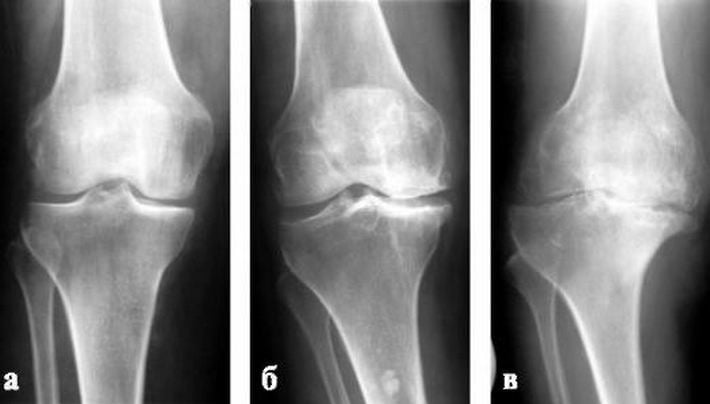

Стадии остеоартроза коленного сустава устанавливаются проведением рентгенографического исследования по произошедшим деструктивным изменениям хрящей и костей. Для каждой из них характерна своя симптоматика — выраженность болевого синдрома, отечности, ограничения подвижности.

1 степень

При остеоартрозе 1 степени колено не видоизменяется. Патология клинически может совсем не проявляться, но чаще все-таки возникают слабые дискомфортные ощущения после долгого нахождения на ногах или положении сидя. Человек считает, что у него просто «затекли» мышцы», поэтому не обращается к врачу. Подвижность колена ограничена незначительно из-за небольшого сужения суставной щели, образования единичных костных наростов.

2 степень

На 2 стадии остеоартроза боли в суставе становятся сильнее, сопровождаются хрустом при движении. Они появляются не только днем, но и в ночные часы. Боли усиливаются при ходьбе, подъеме по лестнице, даже незначительных физических нагрузках. Утром колено выглядит отечным, а движения в нем сильно ограничены. Больному необходимо пройтись по комнате, размяться, чтобы исчезла тугоподвижность. По мере прогрессирования патологии для этого требуется все больше времени из-за умеренной мышечной атрофии, заметного сужения суставной щели, формирования костных наростов, субхондрального остеосклероза костных тканей.

3 степень

Если больной игнорирует все симптомы остеоартроза 1 и 2 степени тяжести, не обращается за медицинской помощью, то суставная щель полностью или частично сращивается. Человек не может полноценно опереться на стопу, при движении использует трость или костыли. Причина тугоподвижности колена заключается в выраженной костной деформации, наличии множественных остеофитов, образовании субхондральных кист и внутрисуставных тел. На завершающем этапе боли даже несколько ослабевают из-за резкого ограничения объема движений.

Наиболее информативна инструментальная диагностика остеоартроза, особенно рентгенографическое исследование. На сделанных в 2 проекциях изображениях хорошо визуализируются остеофиты, разрушенные участки костей, сращение суставной щели. Пациентам может быть назначена КТ для более детального изучения костных суставных поверхностей. Проведение МРТ позволяет выявить степень разрушения гиалинового хряща, оценить состояние мышц, связочно-сухожильного аппарата, кровеносных сосудов, нервов.